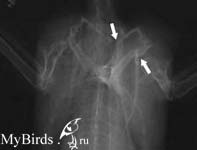

Порванная связка между плечевой костью и плечевым сеставом. Обратите внимание на смещение головки плечевой кости в суставе |

Перелом ключицы и клювовидного отроска:множественные переломы часто происходят при столкновении в полете с препятствием |